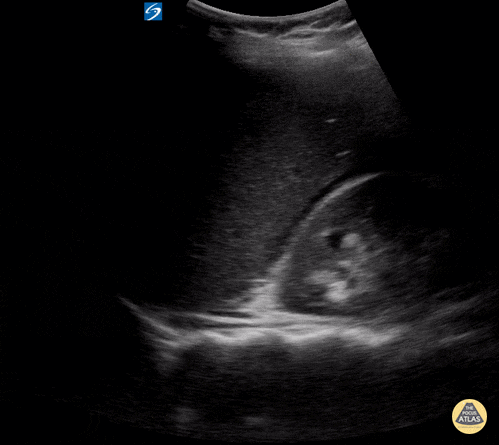

Peds-Trauma - eFAST Positive RUQ

Child with blunt abdominal trauma and free fluid in RUQ. Contributor: Peter Gutierrez, MD FAAP FACEP; Children's Healthcare of Atlanta; @pocuspete